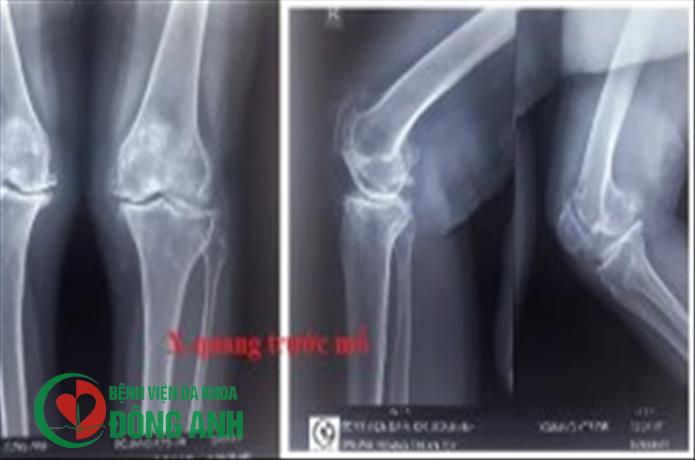

Ca mổ thay khớp gối đầu tiên tại bệnh viện Đa khoa Đông Anh

Ở Việt Nam, thoái hóa khớp gối là một bệnh lý phổ biến ở người có tuổi, là nguyên nhân khiến cho nhiều người bệnh suy giảm khả năng đi lại và lao động, phải chịu đựng sự đau đớn thường xuyên. Thay khớp gối là một phẫu thuật cắt đi lớp sụn đầu xương đã bị hư hoại và thay vào đó là lớp mỏng kim loại bao bọc đầu xương tránh cho xương tiếp xúc trực tiếp với xương gây đau, thay thế cho khớp gối bị hư hại nặng, giúp bệnh nhân phục hồi và vận động bình thường trở lại.